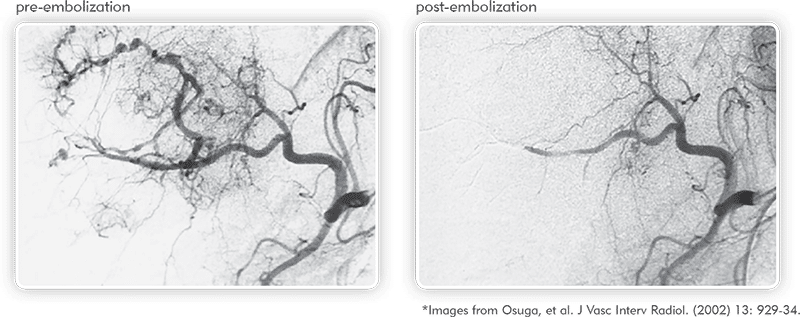

Angiographies of hypervascularized tumor pre- and post-embolization illustrate the ability of QuadraSphere Microspheres to perform a targeted embolization.